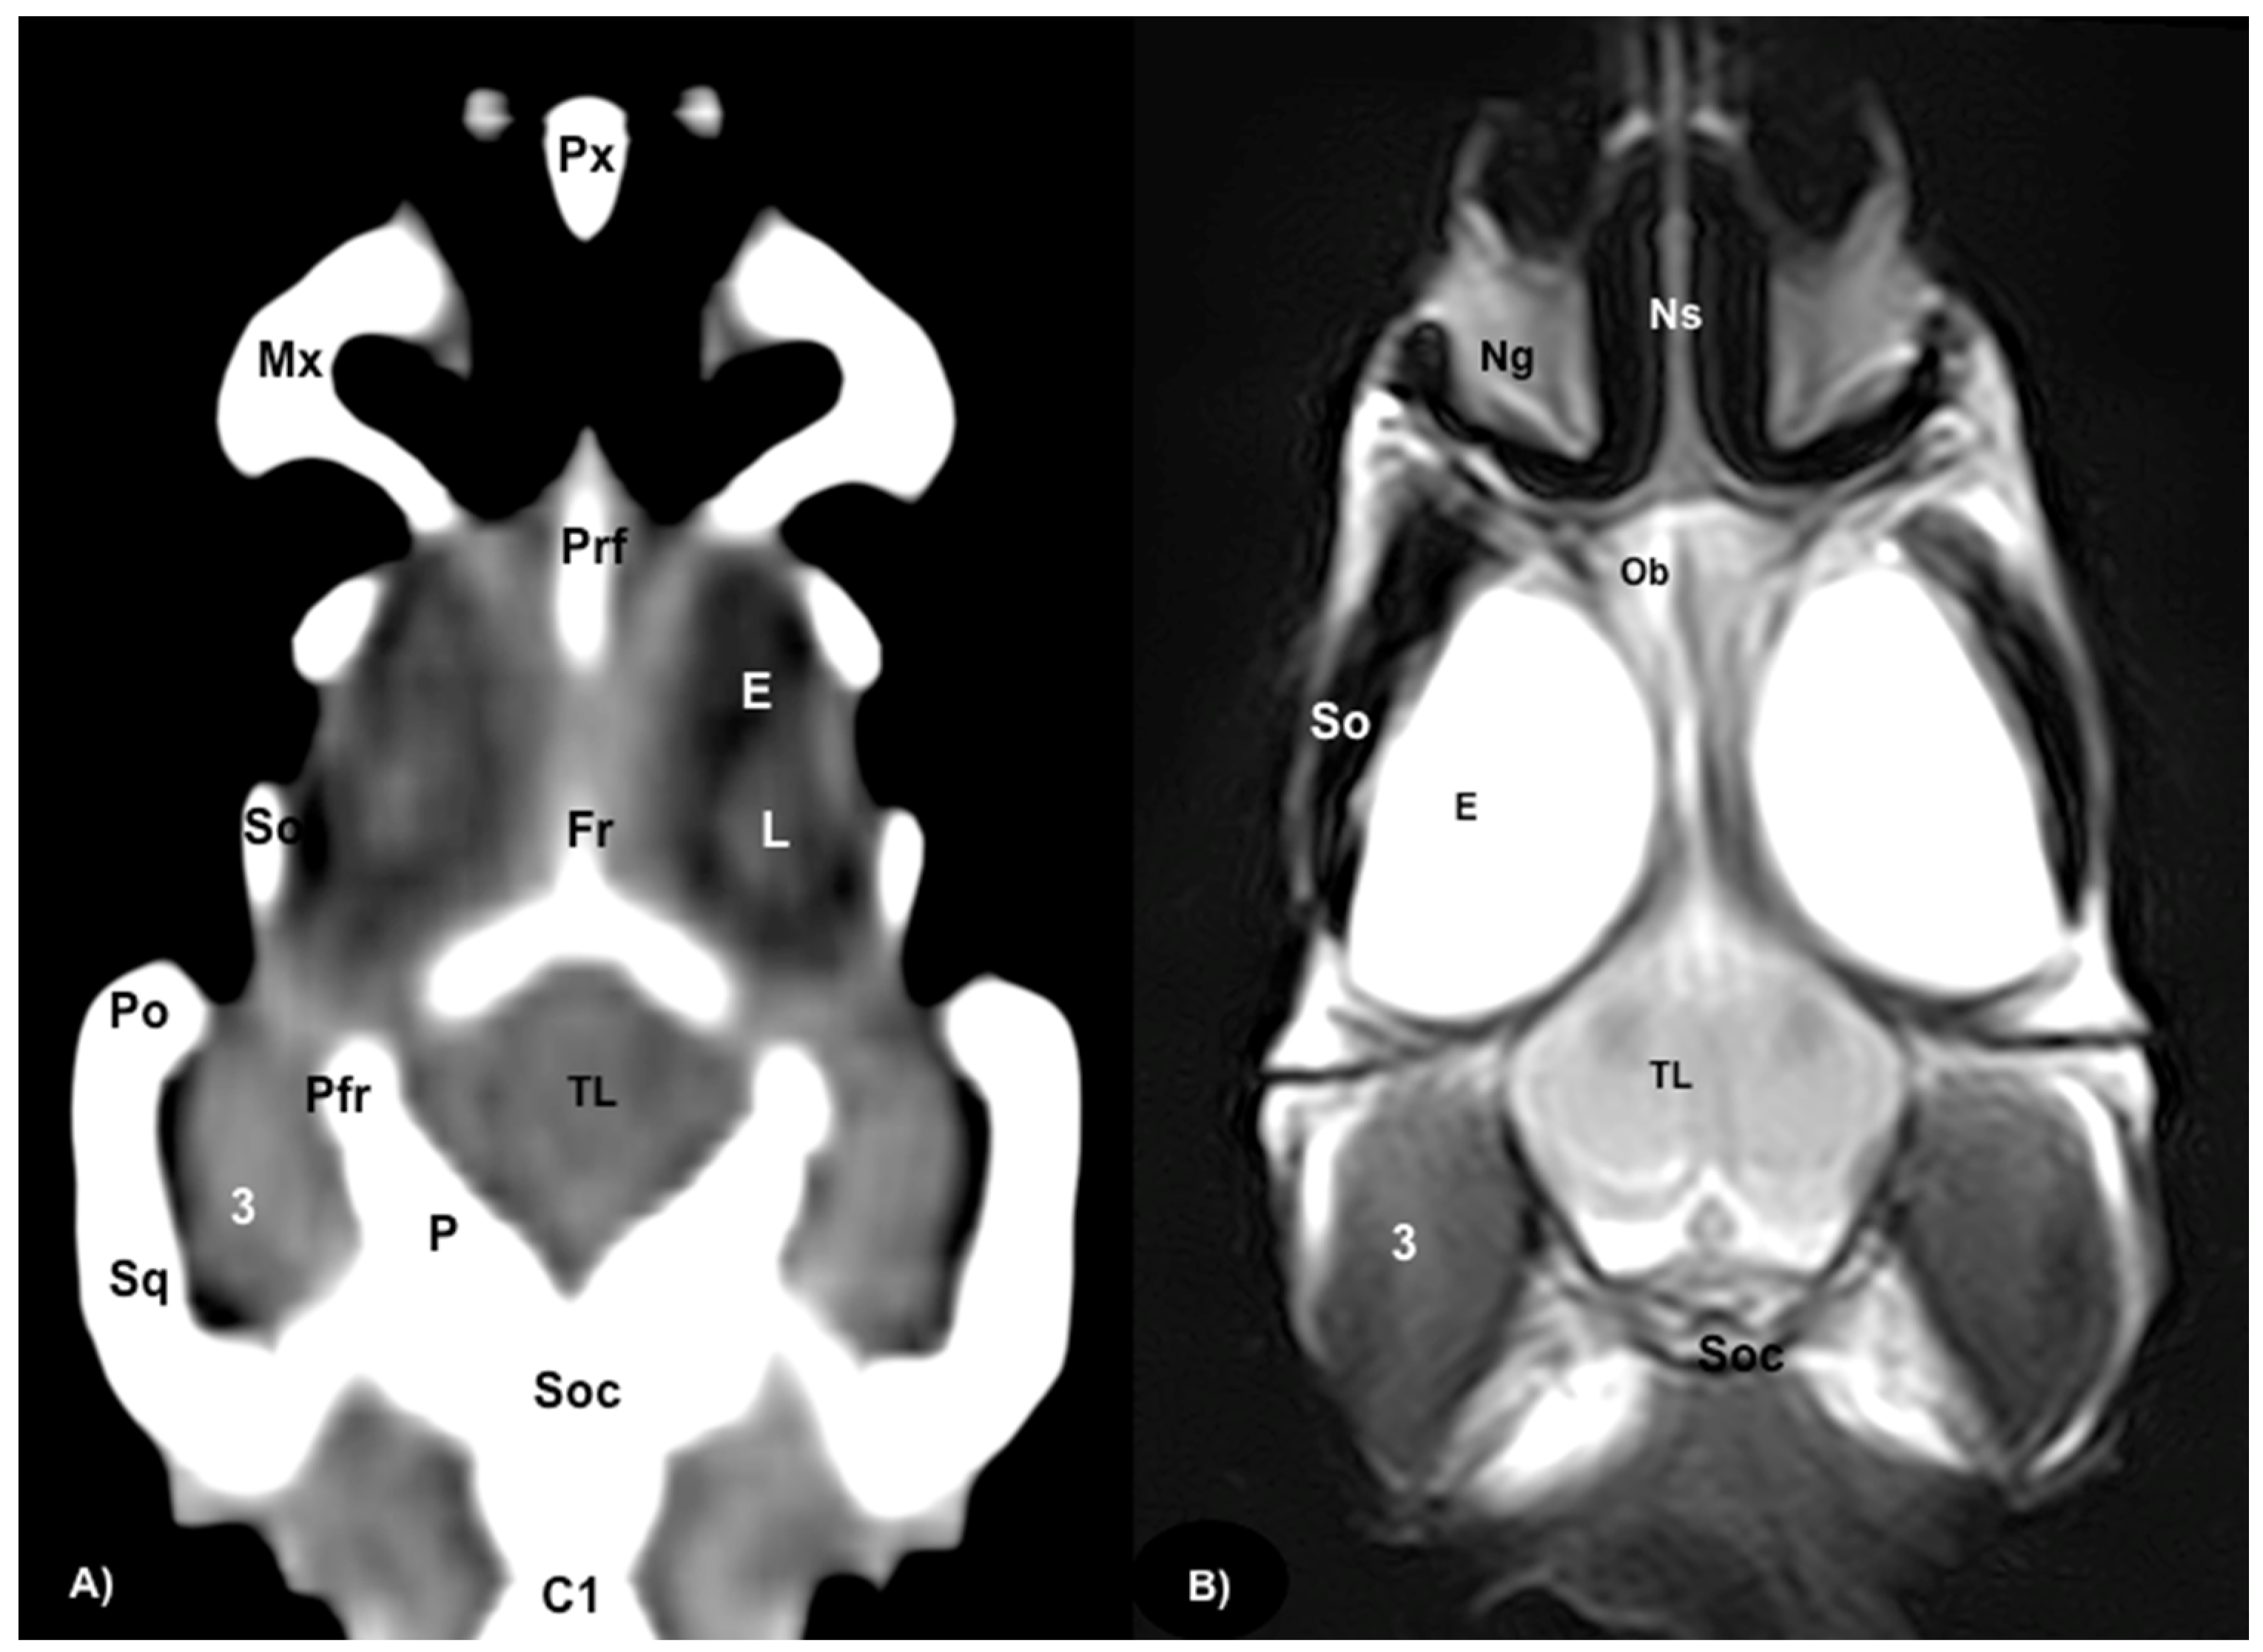

Figure 7.

(A) Dorsal CT image in the brain window. (B) Dorsal MRI in the T2W sequence of the head of rhinoceros iguana telencephalon and at the olfactory bulb level. Px: Premaxillary bone. Ns: Nasal septum. Mx: Maxillary bone. Ng: Nasal glands. Ob: Olfactory bulbs. Prf: Prefrontal bone. E: Eyeball. L: Lens. So: Scleral ossicles. Fr: Frontal bone. TL: Telencephalon. 3: Musculus adductor mandibulae externus medialis. Pfr: Postfrontal bone. Po: Postorbital bone. P: Parietal bone. Soc: Supraoccipital bone. Sq: Squamosal bone. C1: First cervical vertebra.

Different structures belonging to the central nervous system were visualized by anatomical gross-sections. Therefore, we identified the brain (telencephalon) and the two telencephalic hemispheres (Figure 4A and Figure 5A) separated by the fissura longitudinalis cerebri (Figure 5A), the diencephalon (thalamus) (Figure 4A and Figure 5A), the dorsal part of the mesencephalon with the two caudal colliculus (Figure 6A) and the ventral part of the cerebellum with the nodule, covering part of the fourth ventricle, as well as the ventral surface of the brainstem (myelencephalon) (Figure 6A). These sections were also helpful for the observation of the olfactory bulb that showed an extracranial location, ventral to the frontal bones, and coursed between the two eyeballs (Figure 3). In addition, these sections allowed the description of structures of the eyeball, identifying the cornea, the sclera, the retina, the vitreous humor, the lens, as well as associated structures such as the interorbital septum and the orbital sinus (Figure 3A and Figure 4A). In addition, these transverse sections allowed the identification of structures belonging to the oral cavity such as the tongue (Figure 2A) and other structures such as the larynx, with the corniculate tubercles of the arytenoid cartilage, the thyroid cartilage, and the laryngeal ventricle (Figure 3A), as well as of different structures of the nasal cavity such as the nasal glands that filled almost the entire cavity, the conchal grooves and the stammteil located laterally to the nasal septum (Figure 2A). Adjacent structures such as the trachea and the nasopharynx were also well identified (Figure 4A, Figure 5A and Figure 6A). Furthermore, most bony structures that form the neurocranium were observed, such as the pterygoid, frontal, postfrontal-postorbital, parietal, supraoccipital, basioccipital, exoccipital, otoccipital, parabasisphenoid and sphenoid bones (Figure 3A, Figure 4A, Figure 5A and Figure 6A), as well as those that form the splanchnocranium such as the nasal, vomer, palatine and maxillary bones (Figure 2A and Figure 3A) and also the medial horn located dorsal to the nasal bone (Figure 2A), the mandible, with the dentary bone (Figure 3A), and the hyoid apparatus, visualizing the central body of the hyoid arch, between the lateral branches of the dentary bone (Figure 3A). Rostromedially to the two dentary bones, we identified different muscles related to the hyoid apparatus such as the musculus genihyioideus, hyoglossus and intermandibularis (Figure 2A and Figure 3A). In the following sections, we also observed the muscle groups corresponding to the mandibular musculature (we were not able to dissect them, and therefore they were treated as a group), including the pterygoideus, omohyoideus, sternohyoideus, ceratohyoideus, adductor mandibulae externus medialis and its homonym superficialis (Figure 4A and Figure 5A).

Regarding the neurocranium, the CT images allowed us to distinguish bone structures such as the prefrontal, frontal, postfrontal-postorbital, parietal, squamosal, quadrate, epipterygoid, pterygoid, basioccipital, exoccipital, otoccipital and parabasisphenoid bones (Figure 3B, Figure 4B, Figure 5B and Figure 6B); related to the splanchnocranium, we observed the nasal, premaxilla, maxilla, septomaxilla, vomer, jugal and palatine bones, and the nasal septum (Figure 2B, Figure 3B, Figure 4B, Figure 7B and Figure 8B); the mandible structures such as the dentary, angular, surangular, coronoid and articular bones (Figure 2B, Figure 3B, Figure 4B, Figure 5B and Figure 6B) and the hyoid apparatus (Figure 2B, Figure 3B, Figure 4B, Figure 5B and Figure 6B). CT scanning and post-processing transverse images showed the relation between the different bones that form the head of the rhinoceros iguana, the junction of the nasal and the prefrontal bone, as well as that of the parietal bone with the postfrontal-postorbital bone (Figure 2B and Figure 4B), and the palatine and quadrate processes of pterygoid bone (Figure 5B and Figure 6B respectively). The prominent medial horn was identified dorsal to the nasal bone with soft-tissue attenuation and a thin, lamellar-shaped mineral structure bordering it regularly on its most external aspect (Figure 2B).

Concerning the nasal cavity, the transverse CT image showed the nasal glands as symmetrical bilateral structures, with regular and well-defined margins, located on both sides of the nasal cavity and with soft tissue attenuation (Figure 2B). Moreover, those structures with intraluminal gas content such as the nasal conchal recess (Figure 2B), oral cavity, nasopharyngeal duct, trachea, adductor fossa (Figure 4B) and the otic cavity (Figure 6B) were identified with this technique, appearing with a vacuum effect. In addition, there were areas of soft tissue attenuation medial to the mandible and bilateral to the hyoid apparatus, compatible with the intermandibularis, genihyioideus and hyoglossus muscles (1 in Figure 2B and Figure 3B), the pterygoideus, omohyoideus, sternohyoideus and ceratohyoideus muscles (2 in Figure 4B), the adductor mandibulae externus medialis and superficialis muscles located, respectively, dorsomedially and ventrolaterally to the adductor fossa (3 and 4 in Figure 4B and Figure 5B).

3.3. Magnetic Resonance Imaging (MRI)

The soft structures of the iguana’s head, such as the central nervous system as well as the eyeball’s structures (vitreous humor and lens), the oral cavity with the tongue and the masticatory muscles, showed an accurate visualization using MRI (Figure 2C, Figure 3C, Figure 4C, Figure 5C and Figure 6C). Therefore, an increased volume of both eyeballs in proportion to the size of the head was seen in all sequences (Figure 3C and Figure 7B). As in CT, the structures with gas content (Figure 2C and Figure 6C) appeared with a vacuum effect, being hypointense in all sequences. The nasal glands were bilaterally symmetric, with regular and well-defined margins, located on both sides of the nasal cavity, being iso/hyperintense in T1W and T2W sequences, compared to the encephalic grey matter (Figure 2C and Figure 4C). In contrast, the medial horn appeared hypo/isointense on T1W and T2W sequences concerning the white matter and with mild differentiation of the external bony cortex in relation to the white matter (Figure 2C).

In contrast to the CT images, the bone junctions were not distinguishable on MRI, but those bones that formed the neurocranium, such as the frontal, postfrontal-postorbitary, parietal and supraoccipital bones were identified (Figure 3C, Figure 4C, Figure 5C, Figure 6C and Figure 8B). The cranial musculature was found isointense concerning the thalamus in T2W. This technique enabled a better resolution to identify the muscle groups already mentioned (Figure 2C, Figure 3C, Figure 4C and Figure 5C). In the transverse planes of the encephalon, the cerebral cortex was observed slightly more hyperintense than the white matter, which was more hypointense in T2W sequences (Figure 4C). The diencephalic region (Figure 4C, Figure 5C and Figure 8B) was hypointense (T2W) compared to the cerebral cortex (Figure 5C), showing the thalamus and hypothalamus (Figure 8B). The brainstem appeared hypo/isointense in T2W compared to the cerebral cortex, as well as presenting a markedly tortuous horizontal alignment (Figure 8B). Moreover, the caudal colliculus and the fourth ventricle were also displayed in excellent detail. In the rostral aspect of the telencephalon, we distinguished the dorsal pallium rostral part with its lateral and medial portions (Figure 4C). Interestingly, the dorsal MRI image was quite helpful to identify the olfactory bulb located extracranially, which extended rostromedially between the eyeballs (Figure 3C, Figure 7B and Figure 8B).